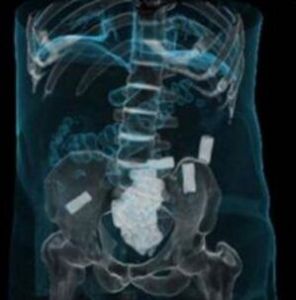

該女子交代其於8月30日吞食毒品海洛因78粒,從成都乘坐K452次列車前往吐魯番,打算在吐魯番站中轉去石河子,9月1日,列車即將到達吐魯番站時,因身體不適,在火車廁所里排出毒品海洛因8粒,因時間緊迫來不及清洗,遂將其暫時放置在內褲中,不料下車後就被民警現場查獲。得知其體內還有毒品後,民警擔心該女子體內海洛因破裂,遂立即將其帶至吐魯番市醫院進行X光檢查,經檢查發現該女子腸道記憶體在大量塊狀物,經工作,該女子又陸續多次從體內排出毒品海洛因70粒,總計78粒。